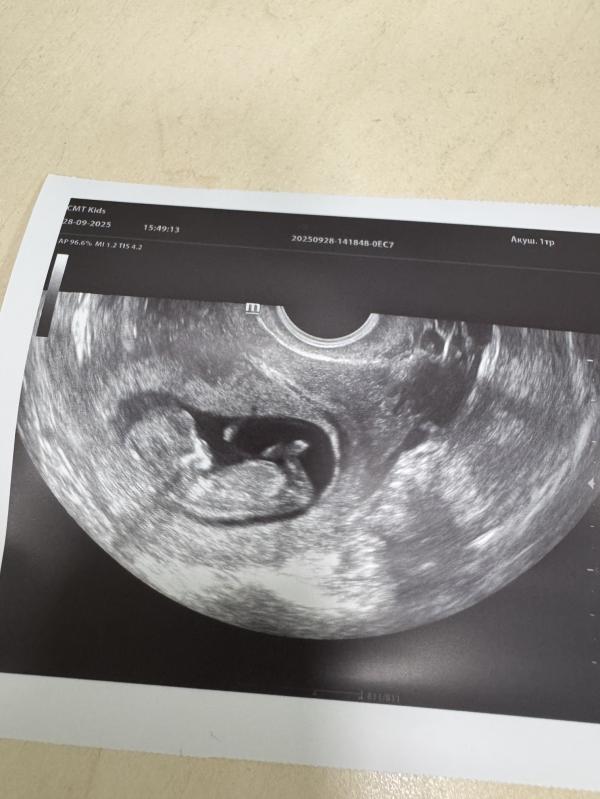

Мне надо восстановить хронологию событий, раз я не стала вести свою страничку с самого начала. УЗИ проходила каждые 2 недели. История развития маленького человека🥰 Последнее фото со скрининга на флотской, лялька с характером, совсем не давалась смотреть и фоткаться😁